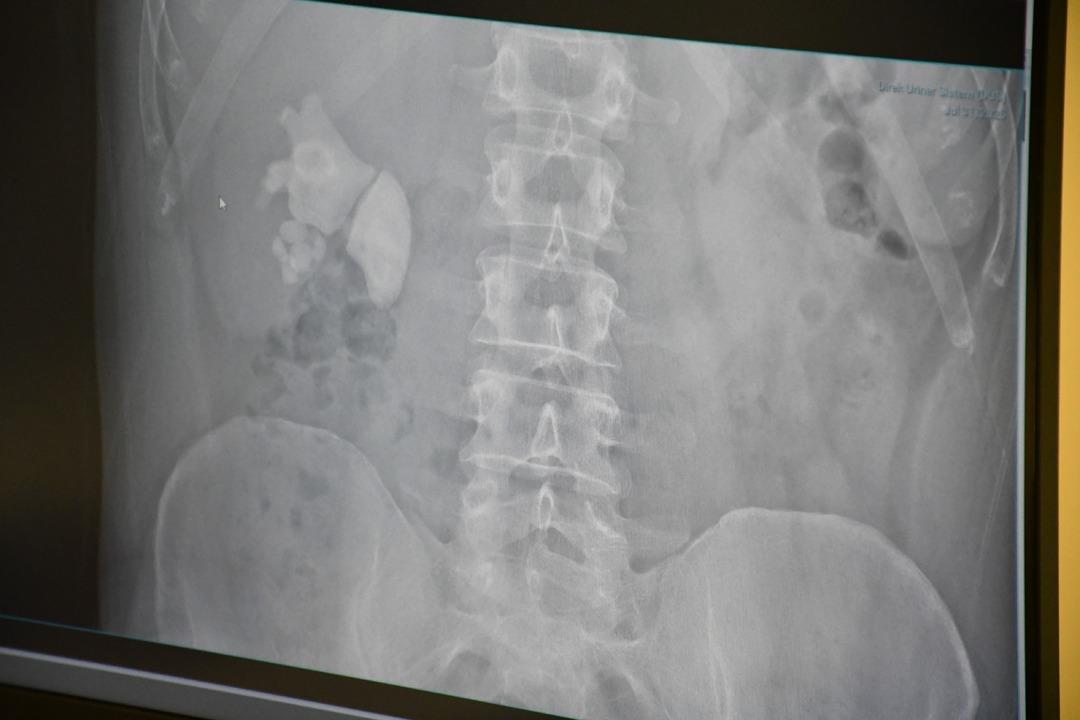

Doktorları şaşkına çeviren vaka: Adamın böbreğinden 100’e yakın taş çıktı: “Sağ böbreğin tamamı taşla doluydu”

Kendilerini şiddetli böbrek ağrısı ile Yozgat şehrinin hastanesine uygulayan Evran’ın ayrıntılı sınavlarının ardından böbrekte yaklaşık 100 taş tespit edildi.

“Tamam böbrek taş doluydu”

Kamocanoglu, “Sağ böbrek muayenemiz taşlarla doluydu. Hasta hastayla tanıştı ve bu kadar büyük taşlarda büyük bir ameliyat olabilir ve hasta bazı deliklere girdi, ameliyatın sırtını gerçekleştirerek yapılması gerektiğini söyledi. Hasta kabul etti. Hasta ameliyatını Çarşamba günü yaptık.”